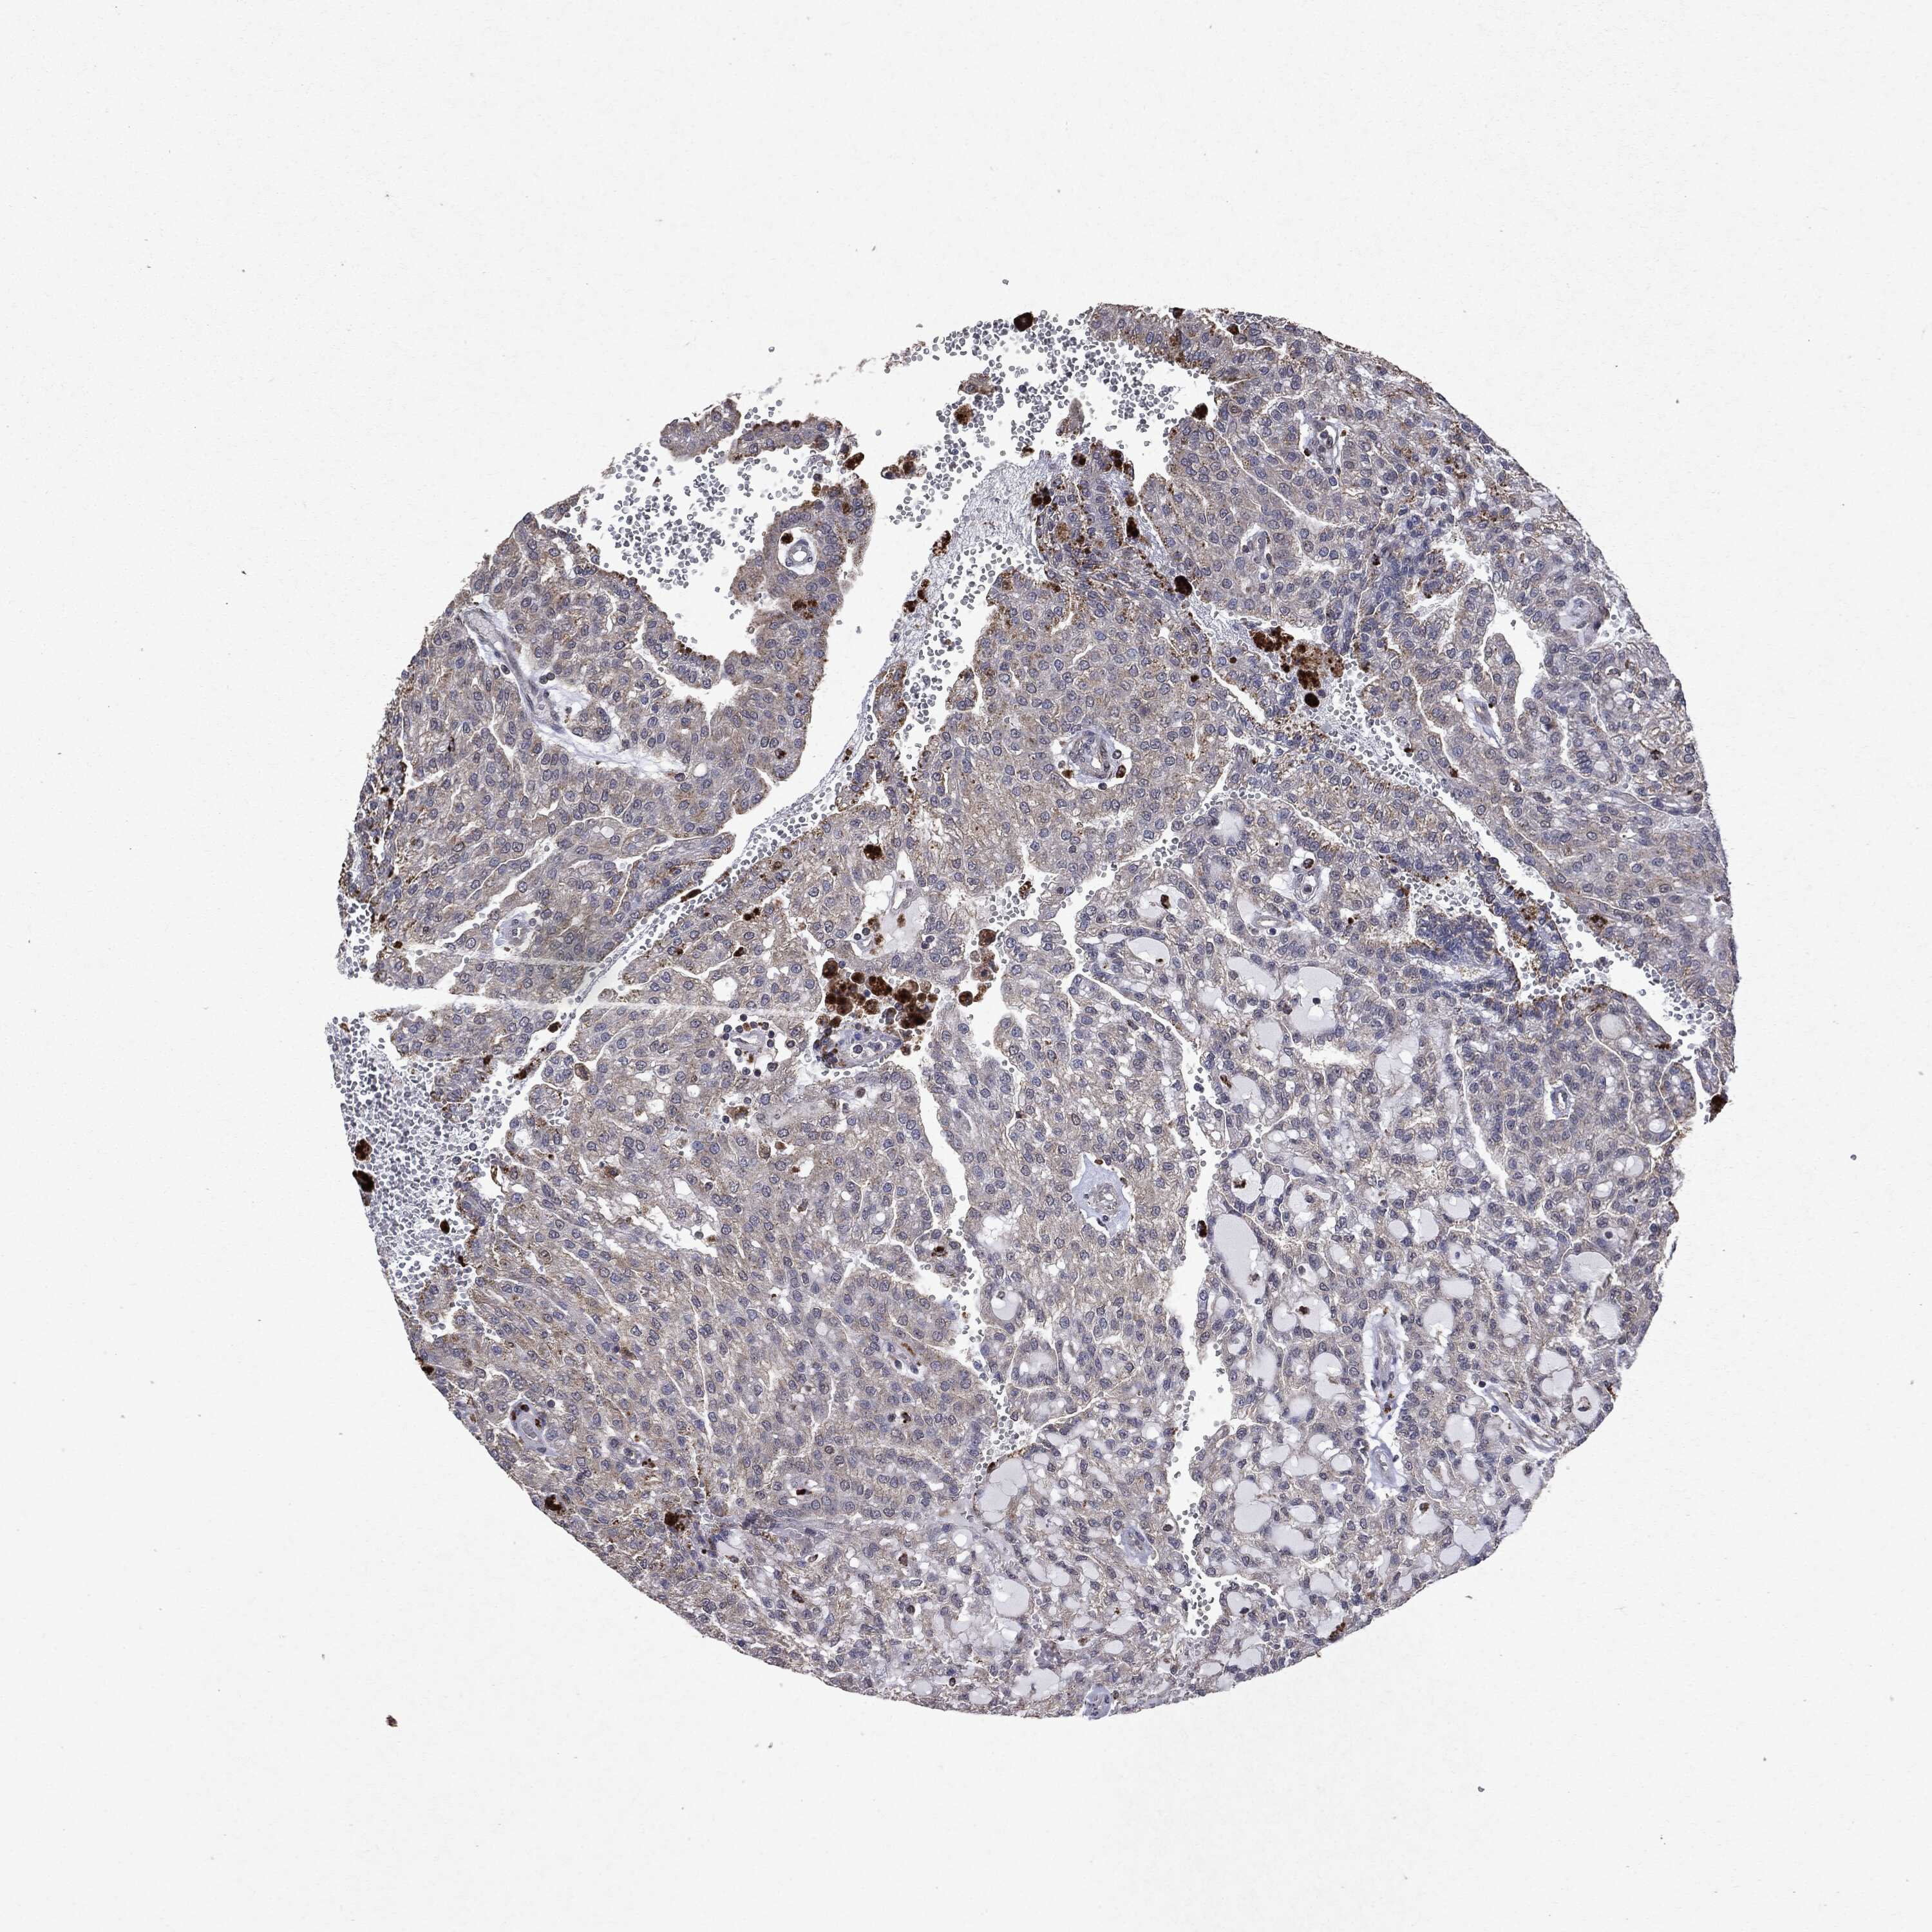

KIDNEY RENAL CLEAR CELL CARCINOMA (VALIDATION) - Interactive survival scatter ploti

The Survival Scatter plot shows the clinical status (i.e. dead or alive) for all individuals in the patient cohort, based on the same data that underlies the corresponding Kaplan-Meier plots. Patients that are alive at last time for follow-up are shown in blue and patients who have died during the study are shown in red.

The x-axis shows the expression levels (FPKM) of the investigated gene in the tumor tissue at the time of diagnosis. The y-axis shows the follow-up time after diagnosis (years). Both axes are complimented with kernel density curves demonstrating the data density over the axes. The top density plot shows the expression levels (FPKM) distribution among dead (red) and alive patients (blue). The right density plot shows the data density of the survived years of dead patients with high and low expression levels respectively, stratified using the cutoff indicated by the vertical dashed line through the Survival Scatter plot. This cutoff is automatically defined based on the FPKM cutoff that minimizes the p-score. The cutoff can be changed by dragging the vertical line or by entering a cutoff value in the square labeled "Current cut-off".

Under the Survival Scatter plot the p-score landscape (black curve; left axis) is shown together with dead median separation (red curve; right axis). Dead median separation is the difference in median mRNA expression between patients who have died with high and low expression, respectively. It is calculated as follows: median FPKM expression of dead patients with high expression - median FPKM expression of dead patients with low expression. This is intended to aid the user in visually exploring custom cutoffs and the associated p-scores and dead median separation.

Individual patient data is displayed and can be filtered by clicking on one or more of the category buttons on the top of the page. Categories describing expression level and patient information include: high, low, alive, dead, female, male and tumor stages. The scale of the x-axis can be toggled between linear and log-scale by clicking on the "x log" button. Mouse-over function shows TCGA ID, patient information and mRNA expression (FPKM) for each patient.

& Survival analysisi

Kaplan-Meier plots summarize results from analysis of correlation between mRNA expression level and patient survival. Patients were divided based on level of expression into one of the two groups "low" (under cut off) or "high" (over cut off). X-axis shows time for survival (years) and y-axis shows the probability of survival, where 1.0 corresponds to 100 percent.

PTEN is not prognostic in Kidney Renal Clear Cell Carcinoma (validation)

Best expression cut offi

Based on the FPKM value of each gene, patients were classified into two groups and association between prognosis (survival) and gene expression (FPKM) was examined. The best expression cut-off refers the FPKM value that yields maximal difference with regard to survival between the two groups at the lowest log-rank P-value. Best expression cut-off was selected based on survival analysis .

When clicking on this number, the vertical dashed line indicating cut-off, the interactive survival plot, and the Kaplan-Meier curve will be adjusted to show results based on the best expression cut-off.

: 26.73

TCGA RNA samplesi

RNA-seq data is reported as average FPKM (number Fragments Per Kilobase of exon per Million reads), generated by the The Cancer Genome Atlas (TCGA) .

Normal distribution across the dataset is visualized with box plots, shown as median and 25th and 75th percentiles. Points are displayed as outliers if they are above or below 1.5 times the interquartile range. FPKM values of the individual samples are presented next to the box plot.

Average pTPM 23.7

Number of samples 100